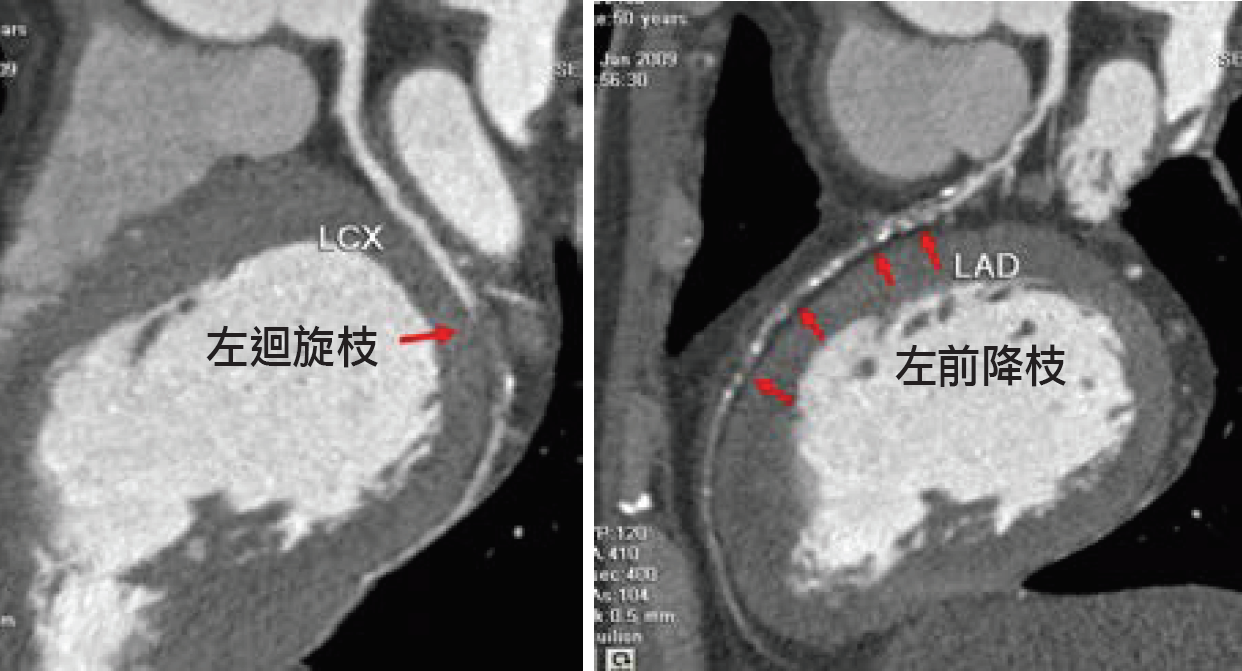

●案例二:52歲男性企業家,經電腦斷層血管攝影檢查,顯示右冠狀動脈及左冠狀動脈迴旋枝均有小段完全阻塞外(箭頭),左前降枝也有一長段呈現阻塞(箭頭),經心導管檢查及支架置放術後,迅速康復。冠狀動脈性猝死(sudden coronary death)較為常見。多鑒於30~49歲的人,男性比女性多3.9倍。